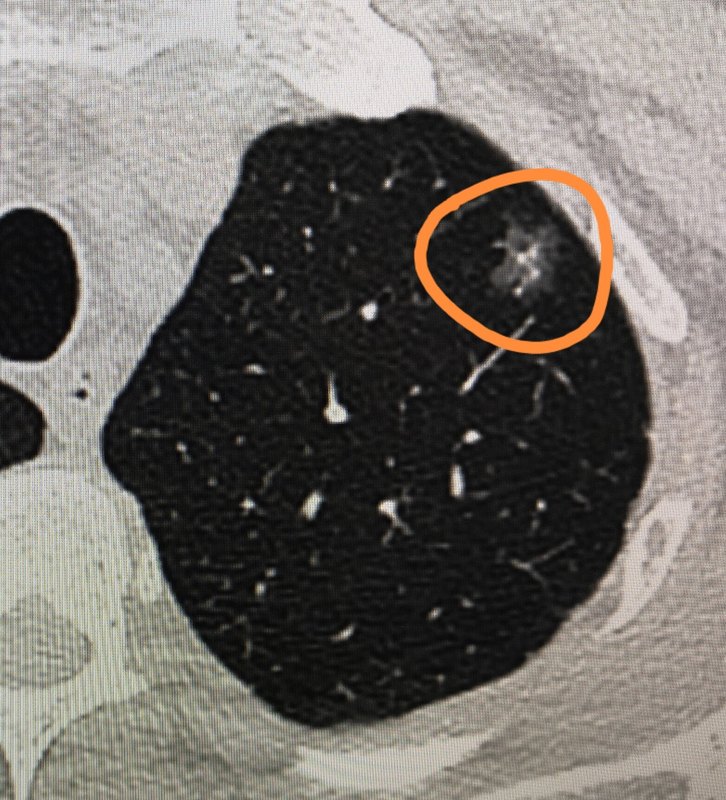

因?yàn)樯磉叺呐笥讯贾牢沂且粋€(gè)胸外科醫(yī)生,所以茶飯之余總會問一些關(guān)于肺癌、肺小結(jié)節(jié)的問題。前幾天,有個(gè)朋友問到了這個(gè)問題,“是不是50歲左右的人肺小結(jié)節(jié)惡性的概率更大?”這里可以給大家簡單分享一下。 首先,對于肺小結(jié)節(jié)是不是肺癌?是不是發(fā)生癌變?其實(shí)跟年齡的關(guān)系并不是很大。 就像我上周做手術(shù)的一位年僅30歲的患者,也是查出肺小結(jié)節(jié),結(jié)合相關(guān)CT檢查,考慮早期肺癌。這是一個(gè)年輕的病人,他就不到50歲!同一天手術(shù)的另外一位50歲的病人,術(shù)前各項(xiàng)檢查都考慮該肺小結(jié)節(jié)是肺癌,結(jié)果手術(shù)后病理結(jié)果卻是良性結(jié)節(jié)。 患者腫瘤的發(fā)生是通過外界致瘤因子作用于機(jī)體,通過長期的刺激,使細(xì)胞的正常生長失去調(diào)控,形成克隆性增殖,最終形成腫瘤。這是一個(gè)長期慢性作用的過程。因此,通常都認(rèn)為,隨著年齡的增長,致瘤因子在機(jī)體的時(shí)間就越久,肺癌發(fā)生的可能性也就越高。我國腫瘤的檢測數(shù)據(jù)也顯示,肺癌的年齡發(fā)病率和死亡率均位于第一位的惡性腫瘤,在40歲以后其發(fā)病率也逐年增高。 但是,美國胸外科協(xié)會的患者宣教材料上,就明確寫著在所有肺結(jié)節(jié)中,早期肺癌肺結(jié)節(jié)的比例不足5%。美國的另外一項(xiàng)針對肺癌CT篩查的研究發(fā)現(xiàn),在5848名年紀(jì)55歲以上、有30年吸煙史的肺結(jié)節(jié)被觀察者中,最終診斷為肺癌的只有234名,比例為4%。顯然,年齡在肺結(jié)節(jié)是肺癌的問題上是重要,但也并不是決定因素。 事實(shí)上,長期吸煙或者二手煙、長期接觸污染空氣、既往有惡性腫瘤的病史、存在惡性腫瘤的家族史,以及肺結(jié)節(jié)的大小、形態(tài)、位置、變化趨勢等等,這些才是目前公認(rèn)的肺小結(jié)節(jié)是肺癌的高危因素。

現(xiàn)在很多人體檢的時(shí)候都會發(fā)現(xiàn)肺結(jié)節(jié),有的接受了手術(shù)治療,有的繼續(xù)隨訪觀察。有的人手術(shù)以后,病理結(jié)果是“原位癌”,而有的是“微浸潤癌”,畢竟心理上總會談癌色變,那么這幾個(gè)名詞,“原位癌”、“微浸潤癌”、“浸潤癌”,同樣都有“癌”字,應(yīng)該都是癌癥,又會有什么區(qū)別呢? 肺結(jié)節(jié)如果是“原位癌”,是指局部肺泡上皮細(xì)胞層內(nèi)的某些細(xì)胞發(fā)生了不典型增生,甚至癌變,但是這些細(xì)胞還沒有穿透基底膜,基底層仍然完整,因而不會發(fā)生轉(zhuǎn)移,切除后也不會復(fù)發(fā)。舉個(gè)例子,就好像一個(gè)橘子,表皮有霉變,但是剝了皮橘子依然是好的,而肺原位癌就類似這種霉變,因此嚴(yán)格意義上來講,它根本算不上真正的癌癥,也不會計(jì)入大病醫(yī)保的范圍。 肺部原位癌還有一個(gè)特點(diǎn),就是生長極其緩慢,大部分保持穩(wěn)定10年以上,只要腫瘤細(xì)胞被正常上皮層的基底膜阻擋,這些癌細(xì)胞就跑不出來,也不會影響其他組織,有時(shí)會持續(xù)很多年,也有可能是終身,所以看到這個(gè)結(jié)果,心里應(yīng)該大舒一口悶氣。 肺原位癌由于細(xì)胞生長規(guī)則,密度均勻,因此在 CT上就是表現(xiàn)為邊界清晰的、均勻的磨玻璃影,不會有實(shí)性成分出現(xiàn),理論上原位癌還會有30%自行退縮的可能。,所以,對于這種可以長期共存共生的肺原位癌類型的肺結(jié)節(jié),只要大小不超過8毫米,或者沒有逐漸生長的趨勢,觀察就好了,如果有變化再考慮手術(shù)切除。 肺“微”浸潤癌,又是什么情況呢? 肺微浸潤癌,重點(diǎn)在于這個(gè)“微”字,是指局部肺泡上皮細(xì)胞層內(nèi)的腫瘤細(xì)胞,開始侵犯鄰近的深層組織細(xì)胞,但是這種浸潤是非常微小的,小于5毫米,所以稱它為微浸潤癌,就像一個(gè)橘子,經(jīng)過一段時(shí)間的霉變之后,沒有得到有效的控制,霉變開始透入與橘皮臨近的果肉中,這時(shí)的橘子必須剝掉壞的那部分才能吃。這種微浸潤癌屬于早期癌癥,只要盡早手術(shù)切干凈,術(shù)后治愈率幾乎100%,術(shù)后往往也不需要放化療或者藥物治療。 肺浸潤癌,是指局部肺泡上皮細(xì)胞層內(nèi)的腫瘤細(xì)胞,開始侵犯鄰近的深層組織細(xì)胞,并且對周圍的浸潤超過了5mm,而且已經(jīng)有了相對豐富的血管供應(yīng),這時(shí)候不但腫瘤會迅速增長,體積逐漸增大,還有可能發(fā)生遠(yuǎn)處轉(zhuǎn)移。就像一個(gè)橘子,霉變已經(jīng)逐漸向深處果肉發(fā)展,甚至已經(jīng)腐爛,這時(shí)候必須果斷地扔掉。對于肺浸潤癌,手術(shù)切除就是王道。